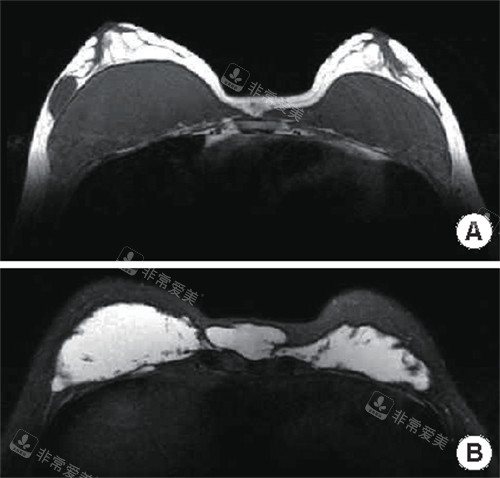

不明注射物在胸部的样子

在面诊过程中,医生会详细了解患者的病史、注射物情况,并通过可靠的检查手段如B超、CT等,确定注射物的具体位置、分布和与周围组织的关系。